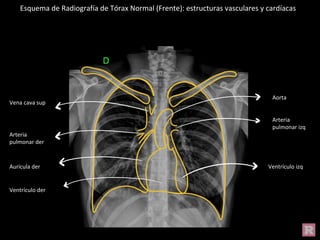

Esquema de Radiografía de Tórax Normal (Frente): estructuras vasculares y cardíacas

Vena cava sup

Arteria

pulmonar der

Aurícula der

Ventrículo der

Aorta

pulmonar izq

Ventrículo izq